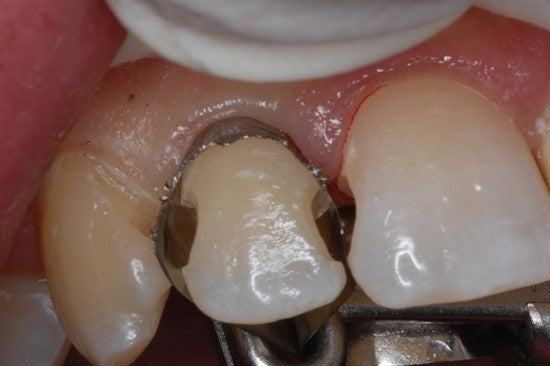

Margin Elevation by Clint K. Taura, DDS

Introduction: This case by Clint Taura, DDS is a wonderful example of how a sectional matrix secured inside a Greater Curve band can provide an excellent subgingival seal and isolation.... Read More